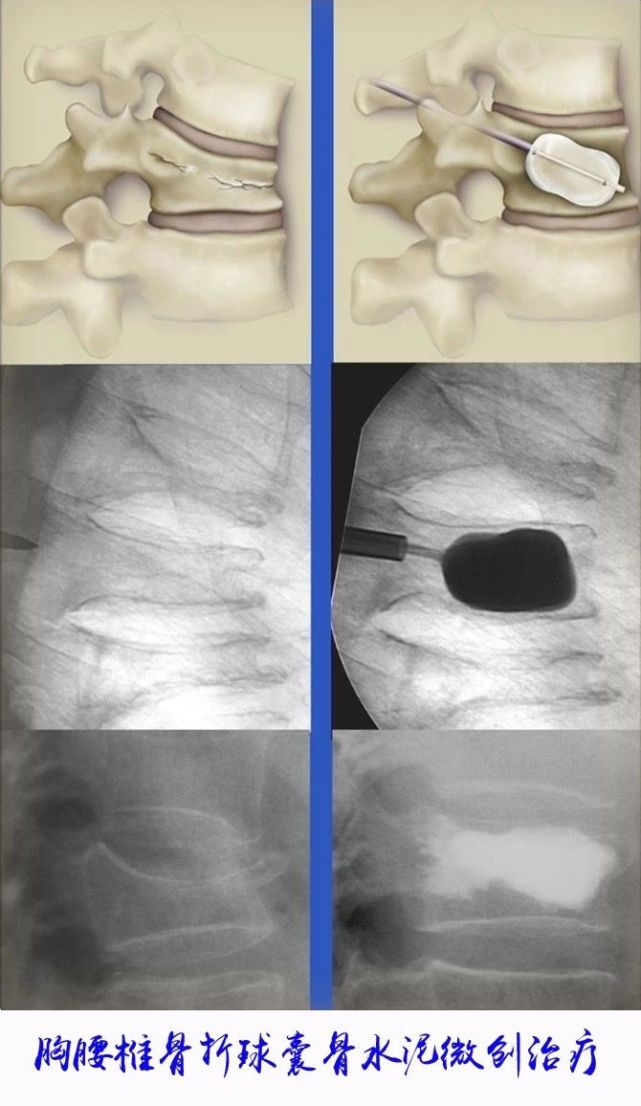

西安唐城医院-骨科 擅长创伤、关节疾病的治疗,专业研究方向为微创骨科及骨坏死,并获得国家发明专利两项

西安交通大学第一附属医院骨科创建于1956年,是西北地区建立最早的骨病与骨创伤专业组,对外称创伤骨科,

创伤骨科:自1911年成立“红十字西北战地医疗救护队”以来,骨科创伤治疗就创伤骨科科研成果丰硕,其中《带